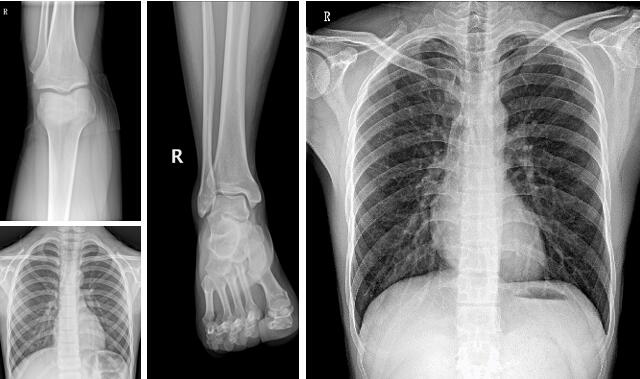

【PLX M5320移动DR临床图像】

3、骨科。操作方便、工作效率高,可移动dr机-PLX M5320可满足人体的头部、四肢、胸腔、脊柱、腰椎、腹部等全身各部位的数字化摄影的工作需求。

PLX M5320采用17×17英寸的大尺寸无线平板探测器,视野宽阔,摆位轻松。16比特灰阶度,稳定输出高分辨率、高解析度的图像。